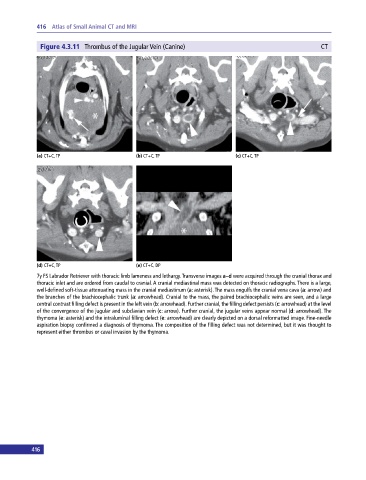

Figure 4.3.11 Thrombus of the Jugular Vein (Canine) CT

(a) CT+C, TP (b) CT+C, TP (c) CT+C, TP

(d) CT+C, TP (e) CT+C, DP

7y FS Labrador Retriever with thoracic limb lameness and lethargy. Transverse images a–d were acquired through the cranial thorax and

thoracic inlet and are ordered from caudal to cranial. A cranial mediastinal mass was detected on thoracic radiographs. There is a large,

well‐defined soft‐tissue attenuating mass in the cranial mediastinum (a: asterisk). The mass engulfs the cranial vena cava (a: arrow) and

the branches of the brachiocephalic trunk (a: arrowhead). Cranial to the mass, the paired brachiocephalic veins are seen, and a large

central contrast filling defect is present in the left vein (b: arrowhead). Further cranial, the filling defect persists (c: arrowhead) at the level

of the convergence of the jugular and subclavian vein (c: arrow). Further cranial, the jugular veins appear normal (d: arrowhead). The

thymoma (e: asterisk) and the intraluminal filling defect (e: arrowhead) are clearly depicted on a dorsal reformatted image. Fine‐needle

aspiration biopsy confirmed a diagnosis of thymoma. The composition of the filling defect was not determined, but it was thought to

represent either thrombus or caval invasion by the thymoma.